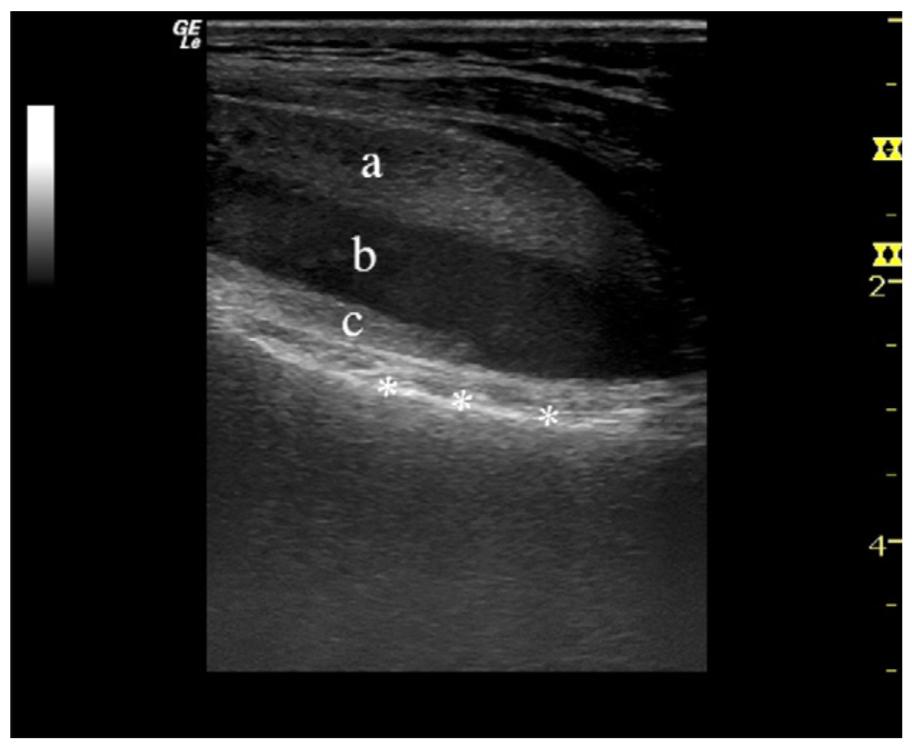

病例2一例左膝外伤患者。在MR横断与矢状位上均可见明显液体分层(见箭头所示)。